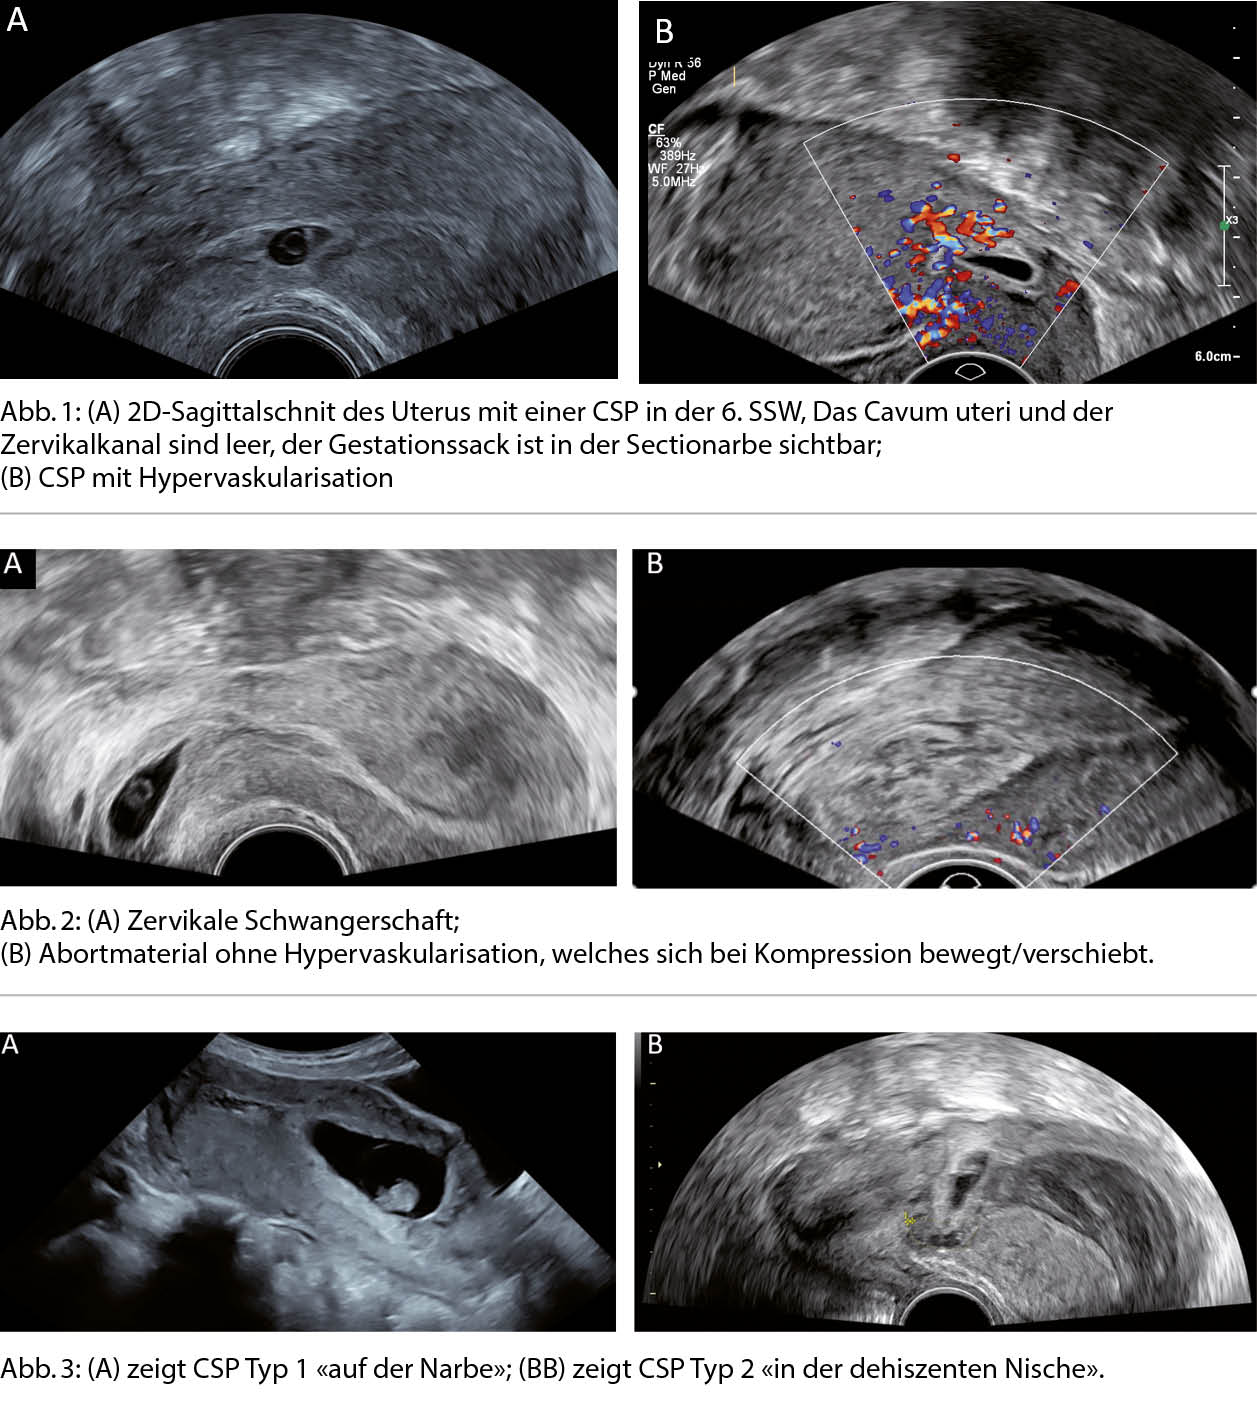

Die CSP kann anhand ihrer Lokalisation verschiedenen Typen zugeordnet werden, von denen man annimmt, dass sie mit dem klinischen Outcome und dem Auftreten von Komplikationen korrelieren. Bei der CSP Typ 1 liegt die Schwangerschaft «auf» der gut geheilten Sectionarbe und mehr als 50% des Gestationssackes ist innerhalb des Endometriums, während bei der CSP Typ 2 die Schwangerschaft «in» der dehiszenten Narbe eingebettet ist und somit mehr als 50% des Gestationssackes ausserhalb des Endometriums in der Wand der Gebärmutter liegt. Aus Schwangerschaften, die man exspektativ gemanaged hat, ist bekannt, dass Schwangerschaften in der Nische (CSP Typ 2) deutlich häufiger zu PAS und Sectiohysterektomien führen als diejenigen, die auf der Narbe liegen (CSP Typ 1) (Abb. 3) (3, 4).